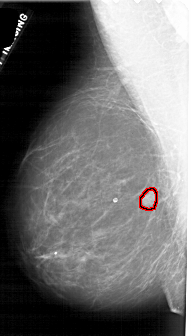

FILE: A_1880_1.LEFT_MLO.OVERLAY

TOTAL_ABNORMALITIES 1

ABNORMALITY 1

LESION_TYPE MASS SHAPE LOBULATED MARGINS OBSCURED

ASSESSMENT 4

SUBTLETY 5

PATHOLOGY BENIGN

TOTAL_OUTLINES 1

BOUNDARY